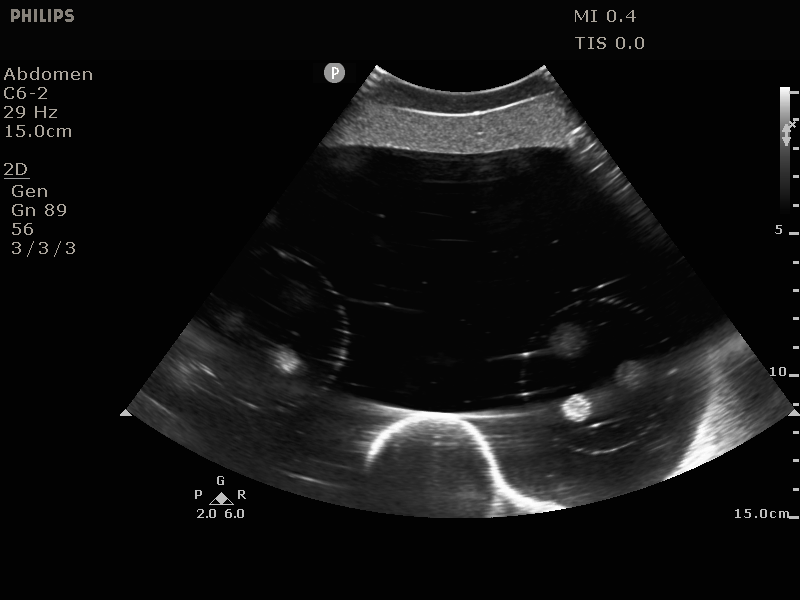

The Image-Guided Abdominal Biopsy Phantom is a simplified abdominal phantom. It’s suitable for training and demonstrating image-guided needle biopsy navigation tools or procedures that require a constant visual reference for needle placement. The phantom allows many uses over time because of the background gel minimizes needle tracks when punctured.

The phantom contains 12 lesions, 5-12 mm in diameter, positioned in groups of three in consistent locations within the phantom. It also includes simulated spine and ribs, and an “H” marker within the spine to assist in determining the head side within a CT-image. You can see the lesions and spine under ultrasound, CT and MRI. The solid polymer gel background is anechoic and will also not leak when it is punctured.

The phantom also includes a foam lined hard carry case and it’s useful in multiple fields. The phantom is perfect for CT, Ultrasound and MRI, live scanning and biopsy training.